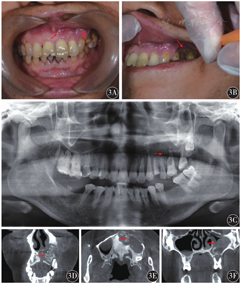

例1,女性,74岁,既往诊断为乳腺癌6年,出现骨转移3年。诊断为骨转移后接受紫杉醇单药化疗,未接受放疗。同期唑来膦酸静脉注射治疗16个月,后因评估肾损伤更换为伊班膦酸静脉滴注给药,并遵医嘱用药10个月余。因下颌处反复溃疡流脓3个月余来我科就诊。追问病史,患者在使用唑来膦酸药物13个月余即出现左下颌尖牙(义齿修复)基牙牙龈退缩,牙根暴露,并出现疼痛。既往无糖尿病史,无放疗史,无颌骨肿瘤病史。临床检查示:颏部皮肤发红、软组织肿胀,正中颏下区可见一皮肤瘘管(图2A),瘘管口变小,探针可探及下颌骨骨面。开口度约1指,左下颌尖牙基牙根暴露,Ⅲ度松动,牙根周边牙龈缺失,牙槽骨暴露(图2B),探诊不出血,表面覆盖少许淡黄白色伪膜。颏部皮肤感觉略迟钝。全景X线摄片示:左下颌尖牙根区大片状骨密度降低及透光区形成,牙根相连牙槽骨局部骨质密度增高(图2C)。螺旋CT示:左下颌局部骨质缺如处可见斑片状游离骨性密度影,下颌骨唇侧、舌侧皮质骨破坏穿通影像(图2D、图2E、图2F)。